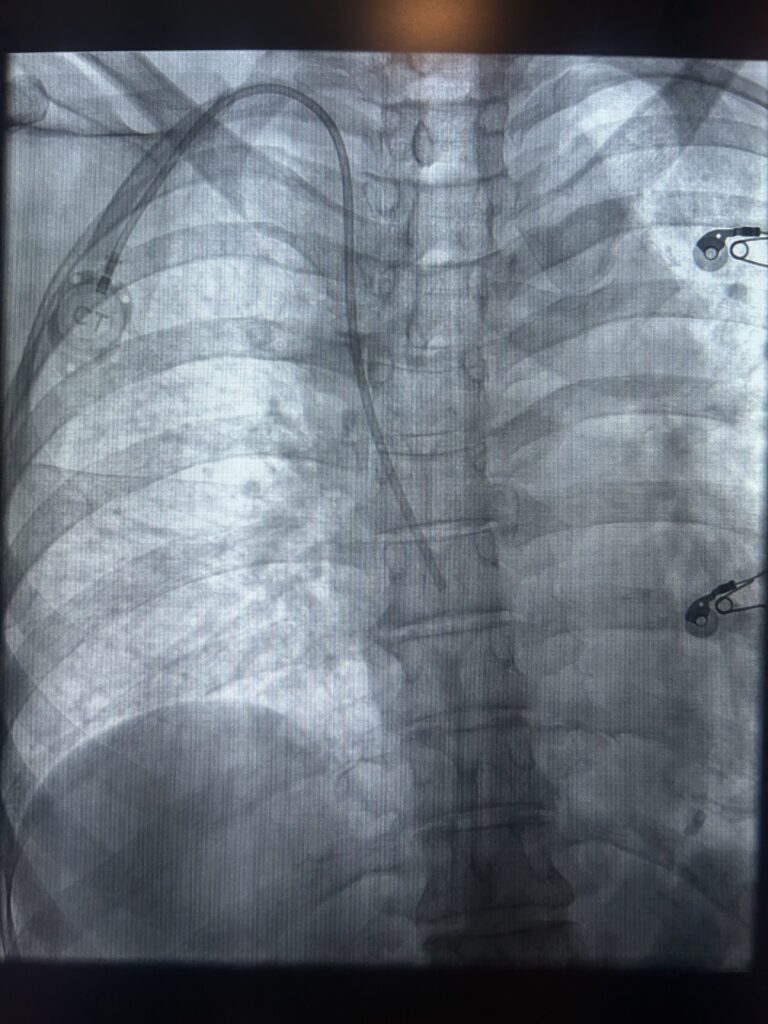

Cateteres de longa permanência são dispositivos médicos finos e flexíveis, introduzidos em uma veia e posicionados, geralmente, em veias de grande calibre próximas ao coração, chamadas veias centrais. Eles permitem a administração de medicamentos, soluções, quimioterapia ou a retirada de sangue de forma repetida, sem a necessidade de múltiplas punções venosas.

A colocação de um cateter de longa permanência é um procedimento médico planejado, realizado em ambiente hospitalar, geralmente em centro cirúrgico ou sala de hemodinâmica, locais que oferecem toda a estrutura necessária para garantir segurança, conforto e controle rigoroso durante a intervenção.

Um dos pilares da técnica moderna é o uso do ultrassom durante a punção venosa. O ultrassom permite o estudo prévio e em tempo real dos vasos sanguíneos, possibilitando a escolha da veia mais adequada em termos de calibre, trajeto e profundidade. Essa avaliação individualizada reduz tentativas de punção, aumenta a precisão do procedimento e contribui diretamente para o bom funcionamento do cateter, maior durabilidade do dispositivo e conforto do paciente.

Após a punção guiada por imagem, o cateter é cuidadosamente introduzido e posicionado em uma veia central, garantindo fluxo adequado e segurança para a administração dos tratamentos. Ao final, o dispositivo é testado e fixado, assegurando sua funcionalidade desde o primeiro uso. Em geral, trata-se de um procedimento de curta duração, com recuperação rápida.